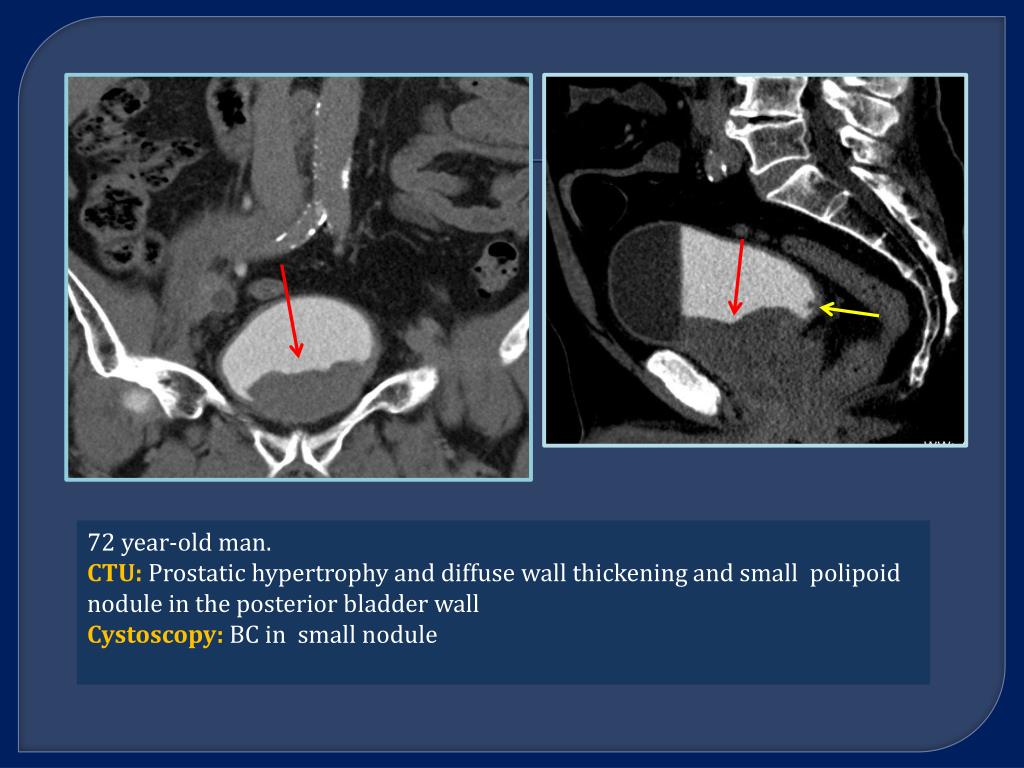

21. 72 year-oldman. CTU: Prostatic hypertrophy and diffuse wall thickening and small polipoid nodule in the posterior bladder wall Cystoscopy: BC in small nodule